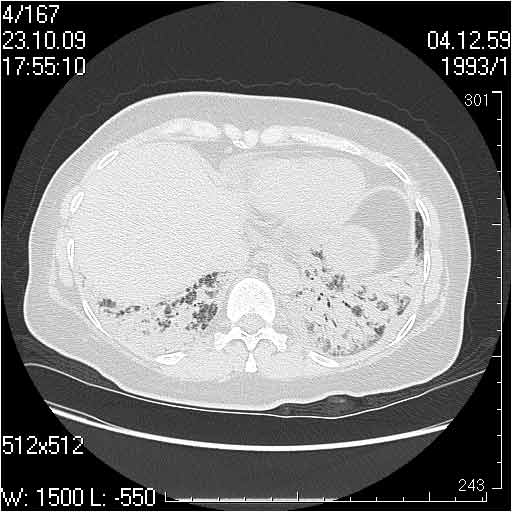

Случай №2

Мужчина 54 лет

Случай 2: картина патологических изменения довольно типична: GGOs & thickened interlobular septas = "crazy paving" sign. Наличие плотностей по типу матового стекла в сочетании с утолщением междолевых перегородок, даёт признак булыжной мостовой; на первом месте будет стоят диагноз альвеолярных протеиноз.